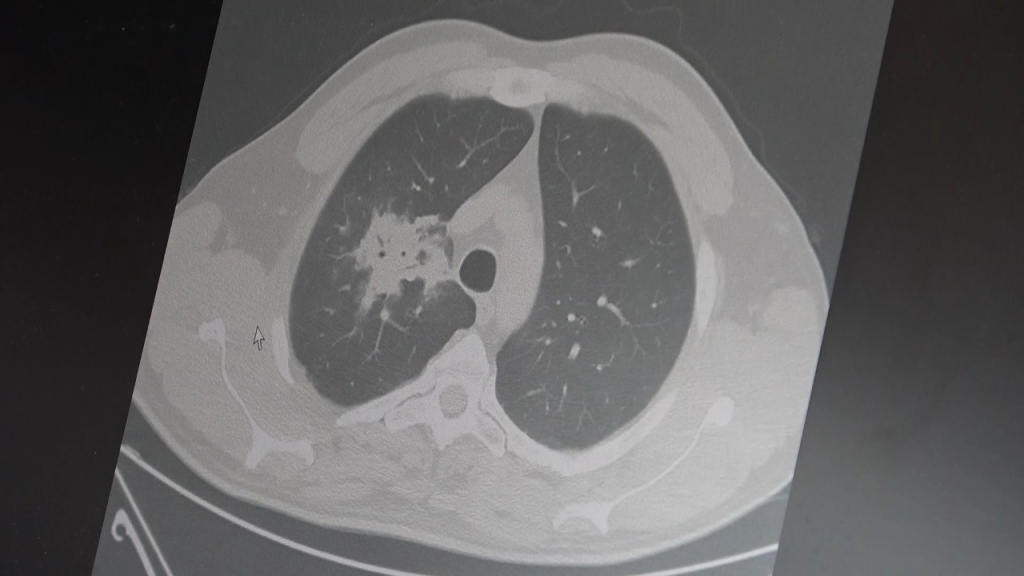

Özkaya, 100’den fazla bilimsel çalışmanın incelendiğini belirterek elektronik sigaraların özellikle akciğer ve ağız bölgelerinde kanser riskini artırabileceğine dair güçlü bulgular bulunduğunu belirtti.

Uzun vadeli sonuçların henüz tam olarak ortaya çıkmadığını ancak erken uyarı işaretlerinin ciddi olduğunu vurguladı.

2024 yılında yayımlanan bir çalışmaya da değinen Özkaya, hem geleneksel sigara hem de elektronik sigara kullanan bireylerde akciğer kanseri riskinin, sadece sigara içenlere göre dört kat daha fazla olduğunun bildirildiğini kaydetti.